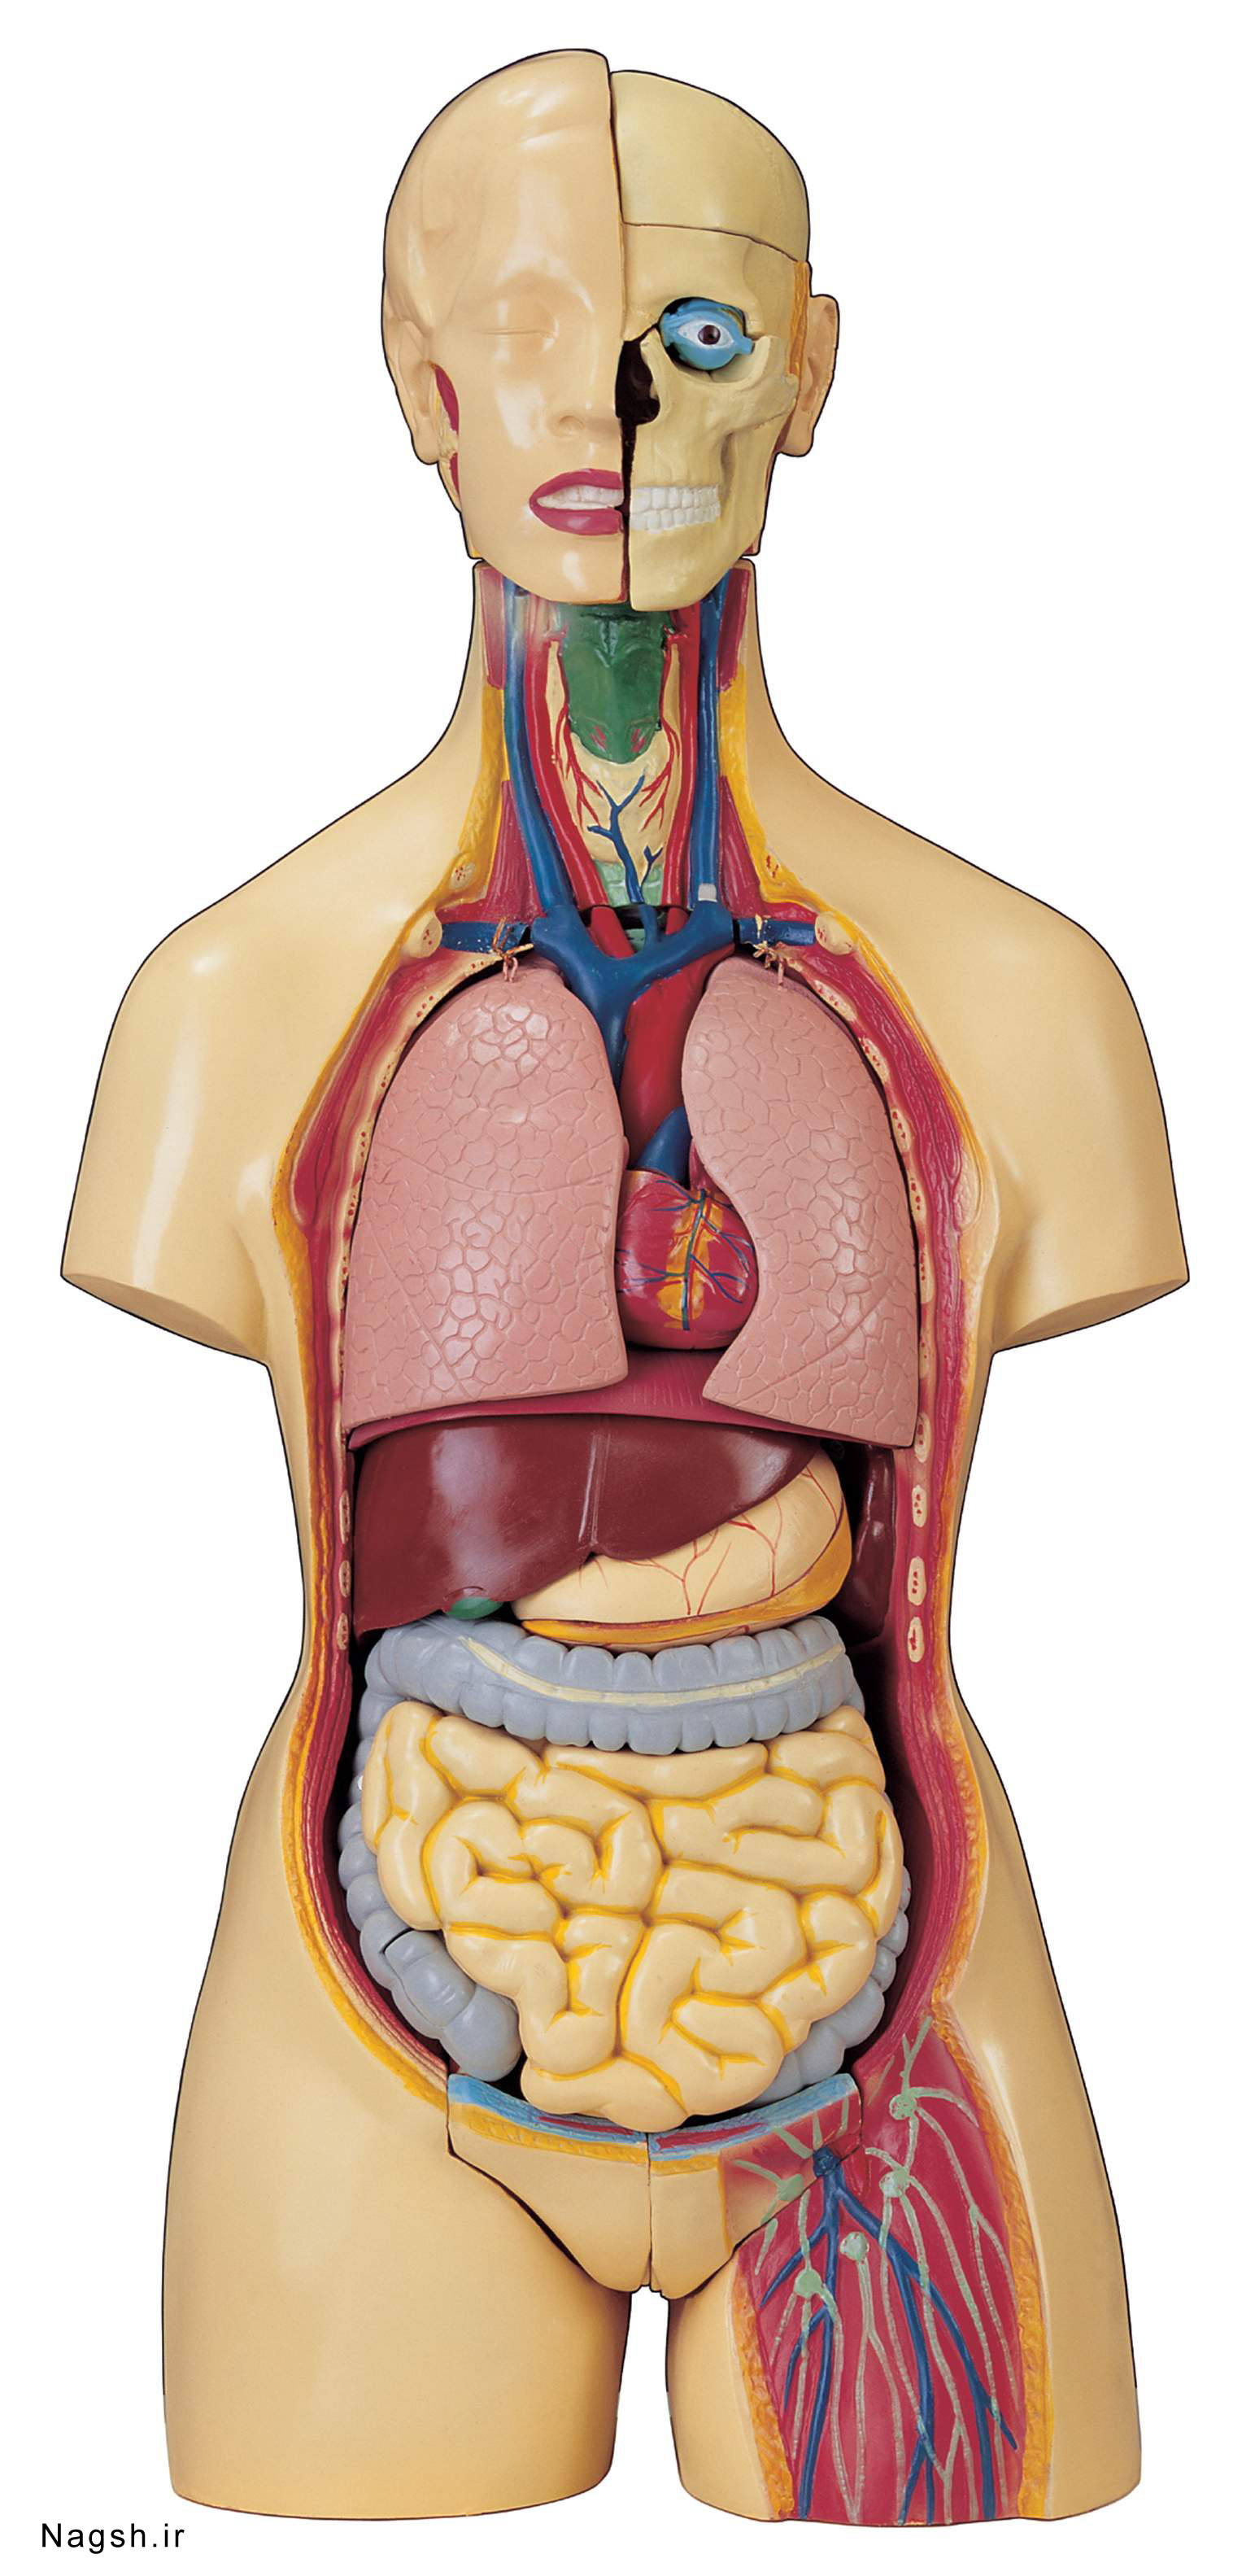

دانلود عکس اسکلت انسان دانلود عکس آناتومی بدن خانم از پشت و جلو دانلود عکس باکیفیت جمجمه انسان.

عکس اسکلت بدن انسان با کیفیت. عکس اسکلت عکس اسکلت برای پروفایل عکس اسکلت انسان عکس اسکلت خفن عکس اسکلت بدن انسان با کیفیت عکس اسکلت بدن انسان عکس اسکلت ترسناک عکس اسکلت فانتزی عکس اسکلت فانتزی دخترانه پرچم عکس اسکلت. عکس با کیفیت اسکلت داخلی انسان و درد و گرفتگی در ناحیه استخوان زانو ویژه استفاده در امور تبلیغاتی و تجاری طراحی کاتالوگ بروشور و تراکت با موضوع پزشکی فیزیوتراپی ارتوپد دکتر روماتیسم فیریوتراپ طب فیزیکی. عکس اسکلت بدن انسان زن و مرد آناتومی ساتین 16 سپتامبر 2017. اسکلت داربست بدن است تمام قسمت های بدن روی اسکلت قرارگرفته اند بدن انسان از ۲۰۶ قطعه استخوان تشکیل شده است این استخوان ها طوری با نظم کنار هم قرار گرفته اند که انسان را قادر می سازد حرکات دقیقی داشته باشد.

اسکلت جمجمه و گردن انسان ستون فقرات آناتومی اسکلت جمجمه و گردن انسان ستون فقرات آناتومی تصویر با کیفیت را از لینک زیر می توانید دانلود کنید. ۱ مطلب با کلمه ی کلیدی عکس اسکلت بدن انسان با کیفیت ثبت شده است گالری نسیم جدید ترین و با کیفیت ترین عکس های مناسبتی. عکس با کیفیت آناتومی اسکلت بدن انسان و درد و دیسک در قسمت مهره های ستون فقرات کمر ویژه استفاده در امور تبلیغاتی و تجاری طراحی کاتالوگ بروشور و تراکت با موضوع بیمارستان ها و کلینیک ها و درمانگاه ها و مطب ها پزشکان و.